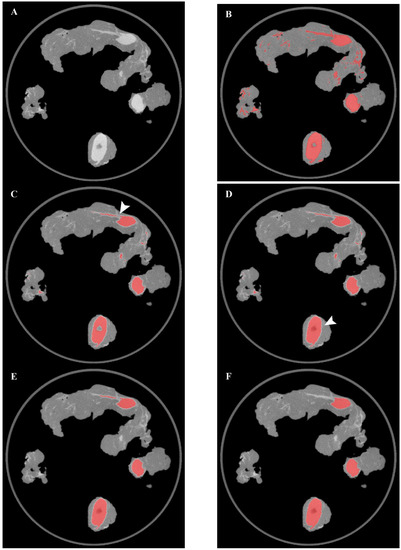

In the operating room, the acquisition of the specimens 68Ga-PSMA-11 PET/CT images with the intraoperative PET/CT scanner proved to be safe and feasible. The median time between radiotracer injection and specimen PET/CT imaging of the pelvic lymph nodes was 125 min. On average, the time required to complete the scanning process of a specimen case was 12 min. Figure 1a,b show the volume rendering of the PET/CT acquisitions, as well as two sample axial slices denoting mild tracer uptake in nodal structures.

Figure 1. (a) Volumetric rendering and axial view (b) of 68Ga-PSMA-11 PET/CT specimen images of the pelvic lymph nodes of a high-risk prostate cancer patient undergoing robot-assisted radical prostatectomy (RARP) and pelvic lymph node dissection (PLND). A, B: left obturator, C: left proximal external iliac, D: left distal external iliac, E: right distal external iliac, F: right obturator, G: right proximal external iliac.

Figure 2. Overview of the results of the main segmentation steps on a sample axial image. (A) original CT image, (B) K-means clustering, (C) Erosion, (D) Filling, (E) 2D noise removal, (F) 3D noise removal. The erosion process allowed to detach two wrongly connected objects (arrow in panel (C)), while the hole-filling operation allowed to include the lymph node hilum in the segmented area (arrow in panel (D)).